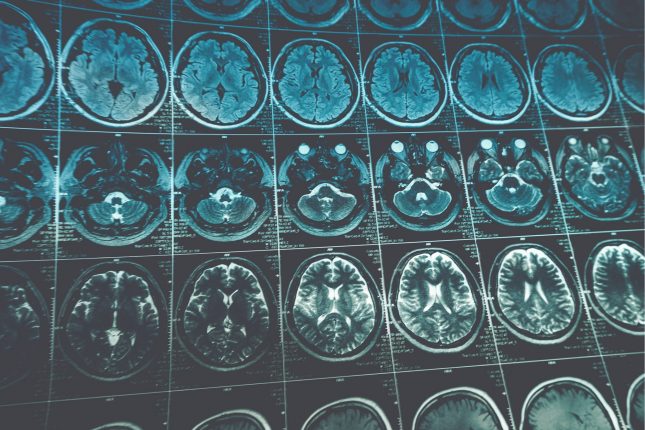

החוקרים מדווחים על אישה צעירה עם סרטן השד בעל ביטוי מוגבר של HER2, עמידות בפני טיפולים סטנדרטיים והתקדמות גרורות למוח. לאישה הושתל רזרבואר ונטריקולרי עבור זריקות intrathecal וביצוע מעקבים פרמקוקינטיים מדויקים אחרי ריכוזי תרופה.

לאישה ניתנו בהתאמה trastuzumab במתן אינטרהטקאלי עם cisplatin תוך ורידי. עבור trastuzumab, ריכוז ממוצע ברזרבואיר נוזל ה-CSF של 53.4 מ"ג/ליטר הביא לרמות רלוונטיות קלינית, מה שאפשר את הייצוב של הגרורות. הוספת cisplatin תוך ורידי לא הועילה, שכן החשיפה לחומר בנוזלי הCSF הייתה נמוכה ביותר וכמעט בלתי ניתנת לגילוי תחת 0.08 מ"ג/ליטר. לאחר מכן המטופלת קבלה שילוב אינטרהטקאלי של trastuzumab ו-methotrexate, בשל ממצאים על סינרגיזם טוקסי של במחקרי in vivo. השיא של רמת methotrexate בנוזל הCNS היה 1037 μmol/L שעתיים לאחר ההזרקה והריכוז נשאר מעל הריכוז הטיפולי התיאורטי. לאחר חודשיים של שילוב תרופתי זה, הושגה תגובה מצוינת של התכווצות הגרורות במוח.